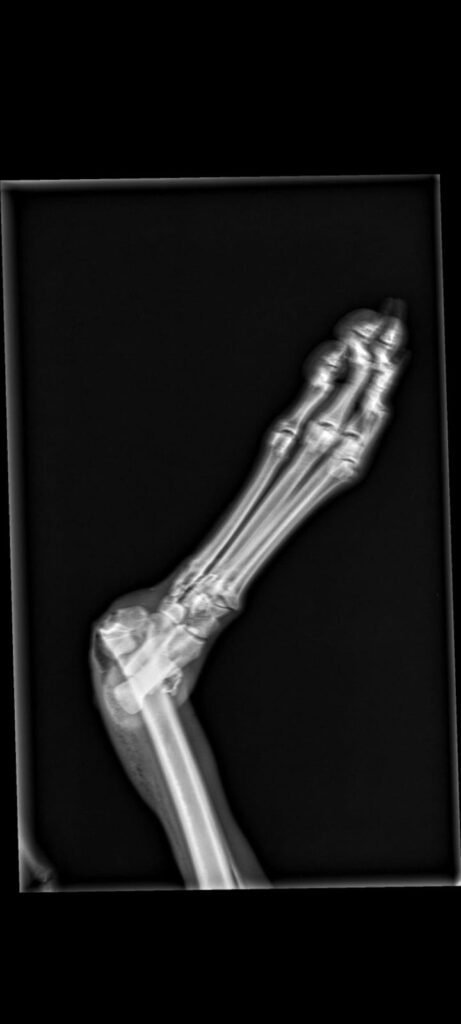

Der Jäger wollte sie einschläfern lassen, weil sie ein gebrochenes Bein hat.

Navidad wurde operiert und die Tierärzte sind mit dem Ergebnis bisher sehr zufrieden. Sie wird alle 2 Tage in der Klinik vorgestellt. Die Wunde ist kaum geschwollen und heilt langsam ab, auftreten tut Navidad bereits auch gut.